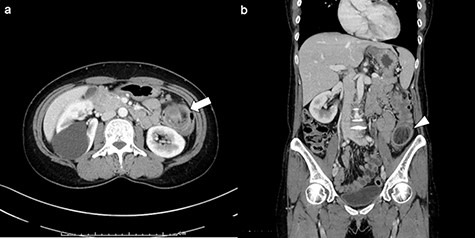

Her body height was 158.0 cm and her weight was 51.0 kg. Her abdomen was soft and without tenderness. There were no palpable tumors. Laboratory tests showed a white blood cell count of 5.3 × 109/L, a red blood cell count of 4.72 × 1012/L, and a hemoglobin level of 14.0 g/dl. Tumor markers such as carbohydrate antigen 19-9 and carcinoembryonic antigen were within normal levels. An abdominal enhanced computed tomography (CT) imaging performed on her first visit revealed a 3.5-cm low-density and low-enhanced tumor with intussusception in the left side of her colon. No swollen lymph nodes around the tumor were detected, and there was no evidence of any tumor invasion or metastasis (Fig. 2). We performed elective surgery for this patient because she had no alarming symptoms. Two weeks after her first visit, the patient was reexamined via abdominal CT scan. There were no findings of intussusception, and the same low-density tumor was found in her left transverse colon near the splenic flexure. Based on the above results, it is likely that the submucosal tumor of the left transverse colon caused intussusception.

Enhanced CT imaging of abdomen: (a) axial view. Three-layer like appearance indicating the intussusception was found in left side of colon (arrow). (b) Coronal view. The lead mass was detected as a 3.5-cm low-density tumor (arrowhead).